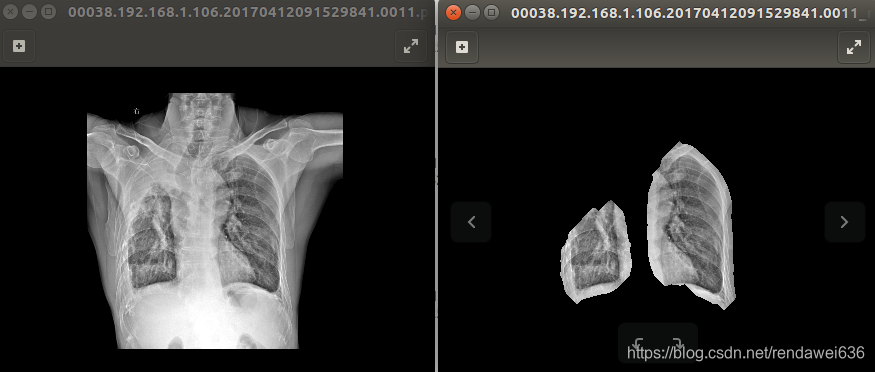

3 和ChexNet不同的是,我们还对影像中的肺部区域进行分割,然后用分割后图像才进行训练。分割所用的模型是UNet基础上加入了ResNet中的短接处理。正常的情况下,肺部的分割效果很不错,如下图所示。但是对于某些病变肺,无论如何效果也不能满足,如图2所示,右上肺产生了实性变,但是分割算法没有识别出来。所以,我们在分割后的图像上又做了些常规的算法处理,最后结果图像,如图3所示。

图2

图3